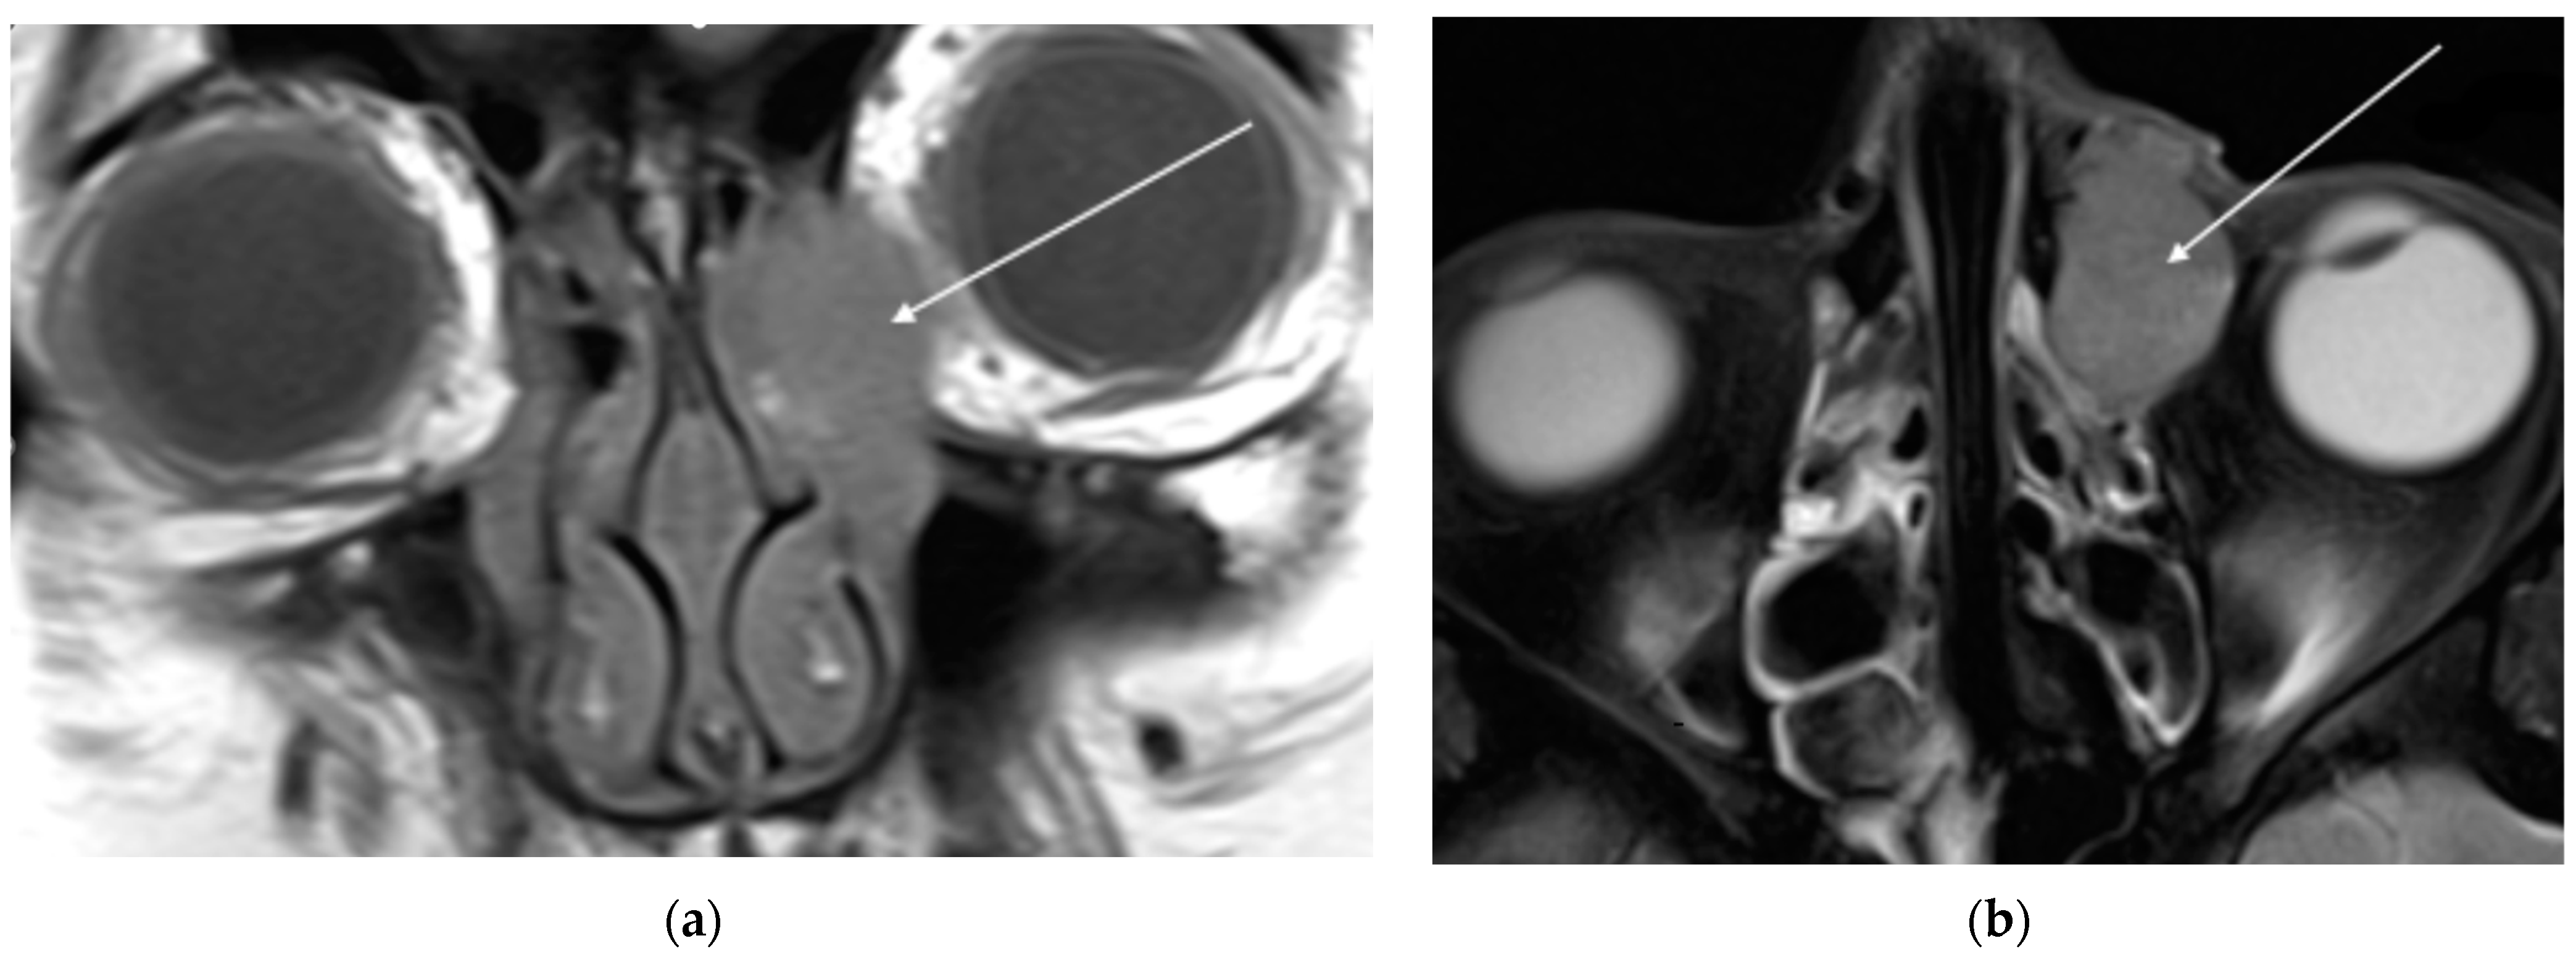

A 51-year-old woman with no comorbidities presented to an ophthalmologist with presbyopia and excessive lacrimation of the left eye for approximately one month. The ophthalmic examination revealed foamy mucus and a papillary reaction of the conjunctiva, which was treated with azithromycin eye drops. At the 4-month follow-up visit, the patient’s symptoms persisted, leading to further antibiotic therapy with erythromycin and ofloxacin drops. Five months after the primary consultation, the patient was admitted to the ophthalmology department with edema of the medial angle of the left eye and mild (3/10) left ocular pain radiating to the forehead and maxilla. During hospitalization, the lesion was incised, but no tissue sample was taken for histopathology. Head magnetic resonance imaging (MRI) was performed. The MRI revealed a solid, well-demarcated lesion, measuring 24 × 14 × 25 mm, located in the left LS fossa (Figure 1). The finding showed moderate enhancement after contrast and moderately restricted diffusion. The tumor mass extended into the dilated left lacrimal canal and ethmoidal bulla. The left middle nasal concha and left orbit were, consequently, modulated. No abnormal lymph nodes were observed.

Figure 1. The MRI T1 (a); and T2 (b) projections of a 51-year-old woman demonstrate a solid, lesion in her left lacrimal sac fossa, indicated by the white arrow.